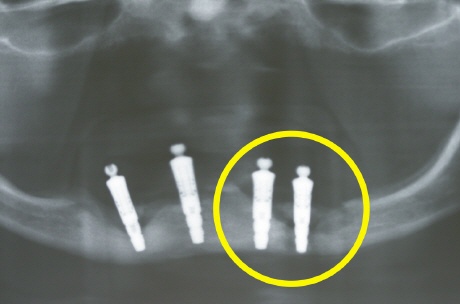

Heftiger Knochenabbau (Risiko Kieferfraktur)

Das Röntgenübersichtsbild zeigt nichts Gutes. Die dunklen Bereiche um die Implantate (helle "Stifte") spiegeln den daramtischen Knochenabbau wieder. Besonders am ganz rechten Implantat (gelber Kreis) reicht dieser Knochenabbau schon durch den gesamten Unterkeiferkörper. Es besteht hierbei ein sehr hohes Risiko für eine entzündungsbedingte Kieferfraktur (sog. pathologische Fraktur).